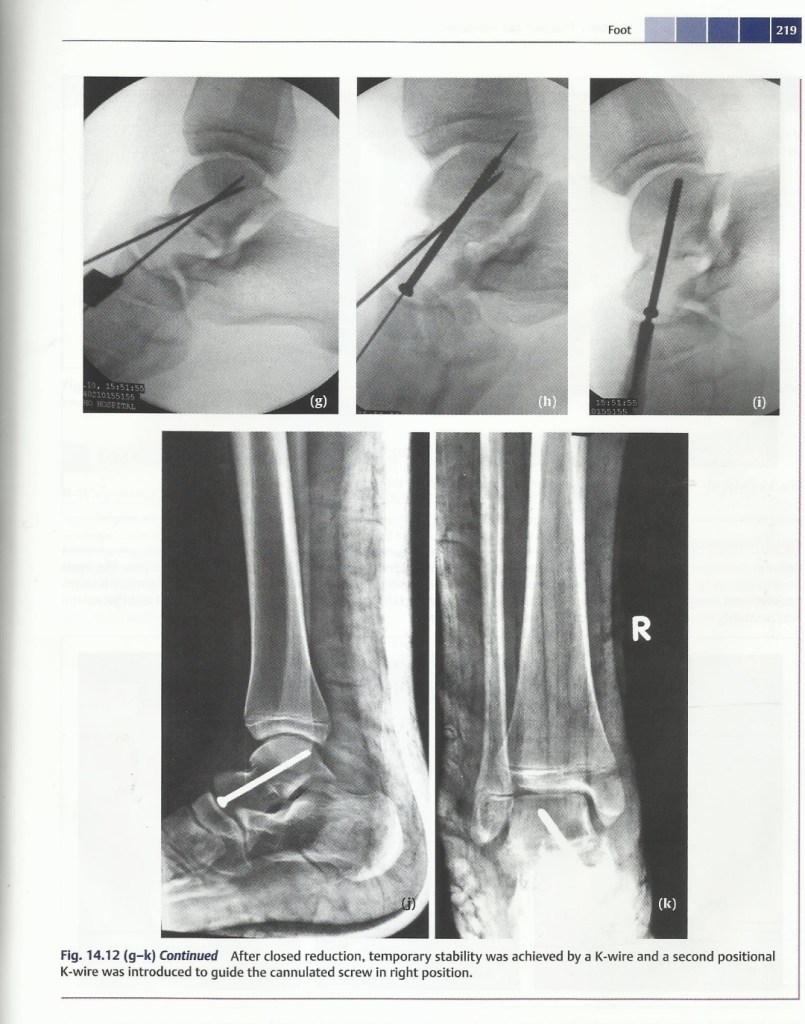

Talus fracture & Subtalar dislocation